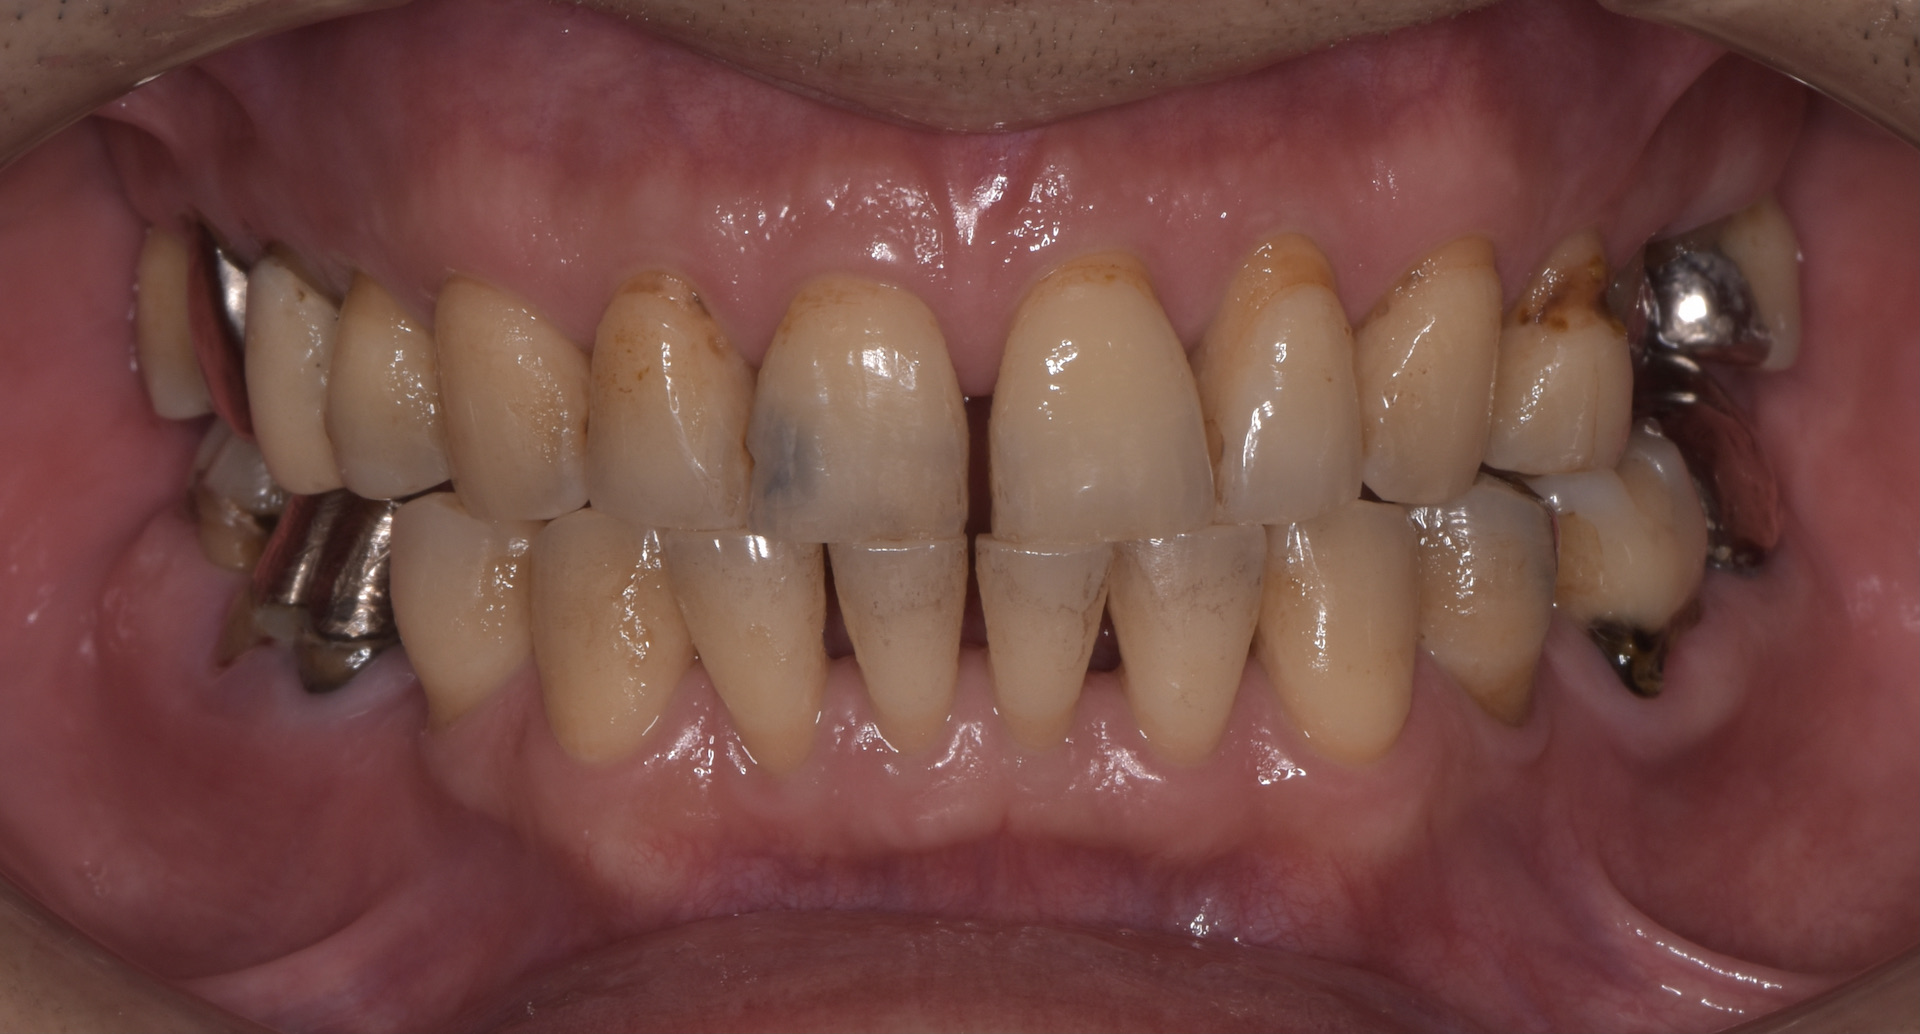

治療前

この患者さんは長年、首都圏の顎関節専門医のもとに通院しておられたそうです。この専門医の治療は従来のスプリントによる顎関節症治療でした。しかし、治療期間が長くなっても全く改善の兆しが無いため、紹介にて名取歯科医院に来院されました。